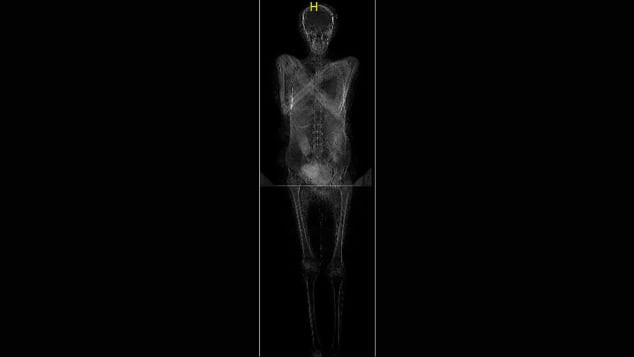

Các chuyên gia mới công bố phát hiện xác ướp mang thai đầu tiên trên thế giới. Thi hài này có niên đại vào thế kỷ thứ nhất tại Ai Cập. Người phụ nữ qua đời khi mang thai khoảng 6,5 - 7,5 tháng.

Các nhà khảo cổ học thuộc Học viện Khoa học Ba Lan làm việc trong Dự án Xác ướp Warsaw tiến hành quét tất cả các xác ướp được lưu giữ và bảo quản trong các bảo tàng. Trong quá trình đó, họ phát hiện ra xác ướp mang thai đầu tiên trên thế giới.

Theo các chuyên gia, xác ướp thuộc về một phụ nữ qua đời khi khoảng 20 - 30 tuổi. Tử cung của người này có một bào thai khoảng 6,5 - 7,5 tháng tuổi.

Đây là lần đầu tiên các chuyên gia tìm thấy xác ướp mang thai. Vì vậy, họ chưa thể lý giải được vì sao thai nghi được giữ trong tử cung của người phụ nữ thay vì ướp xác riêng. Bởi lẽ, thông thường, khi ướp xác, người Ai Cập thời cổ đại thường loại bỏ tim, phổi, gan và ruột cùng dạ dày trong cơ thể và đem ướp xác riêng. Thai nhi cũng như vậy.

Thông qua một số kiểm tra, các chuyên gia xác định niên đại của xác ướp mang thai này khoảng 2.000 năm tuổi. Sau khi qua đời, người phụ nữ được ướp xác. Bên ngoài xác ướp được bọc bằng vải chất lượng cao cùng loạt bùa hộ mệnh tượng trưng cho "Bốn người con của Horus". Điều này cho thấy người phụ nữ đó có địa vị quan trọng ở Thebes hơn 2.000 năm trước.